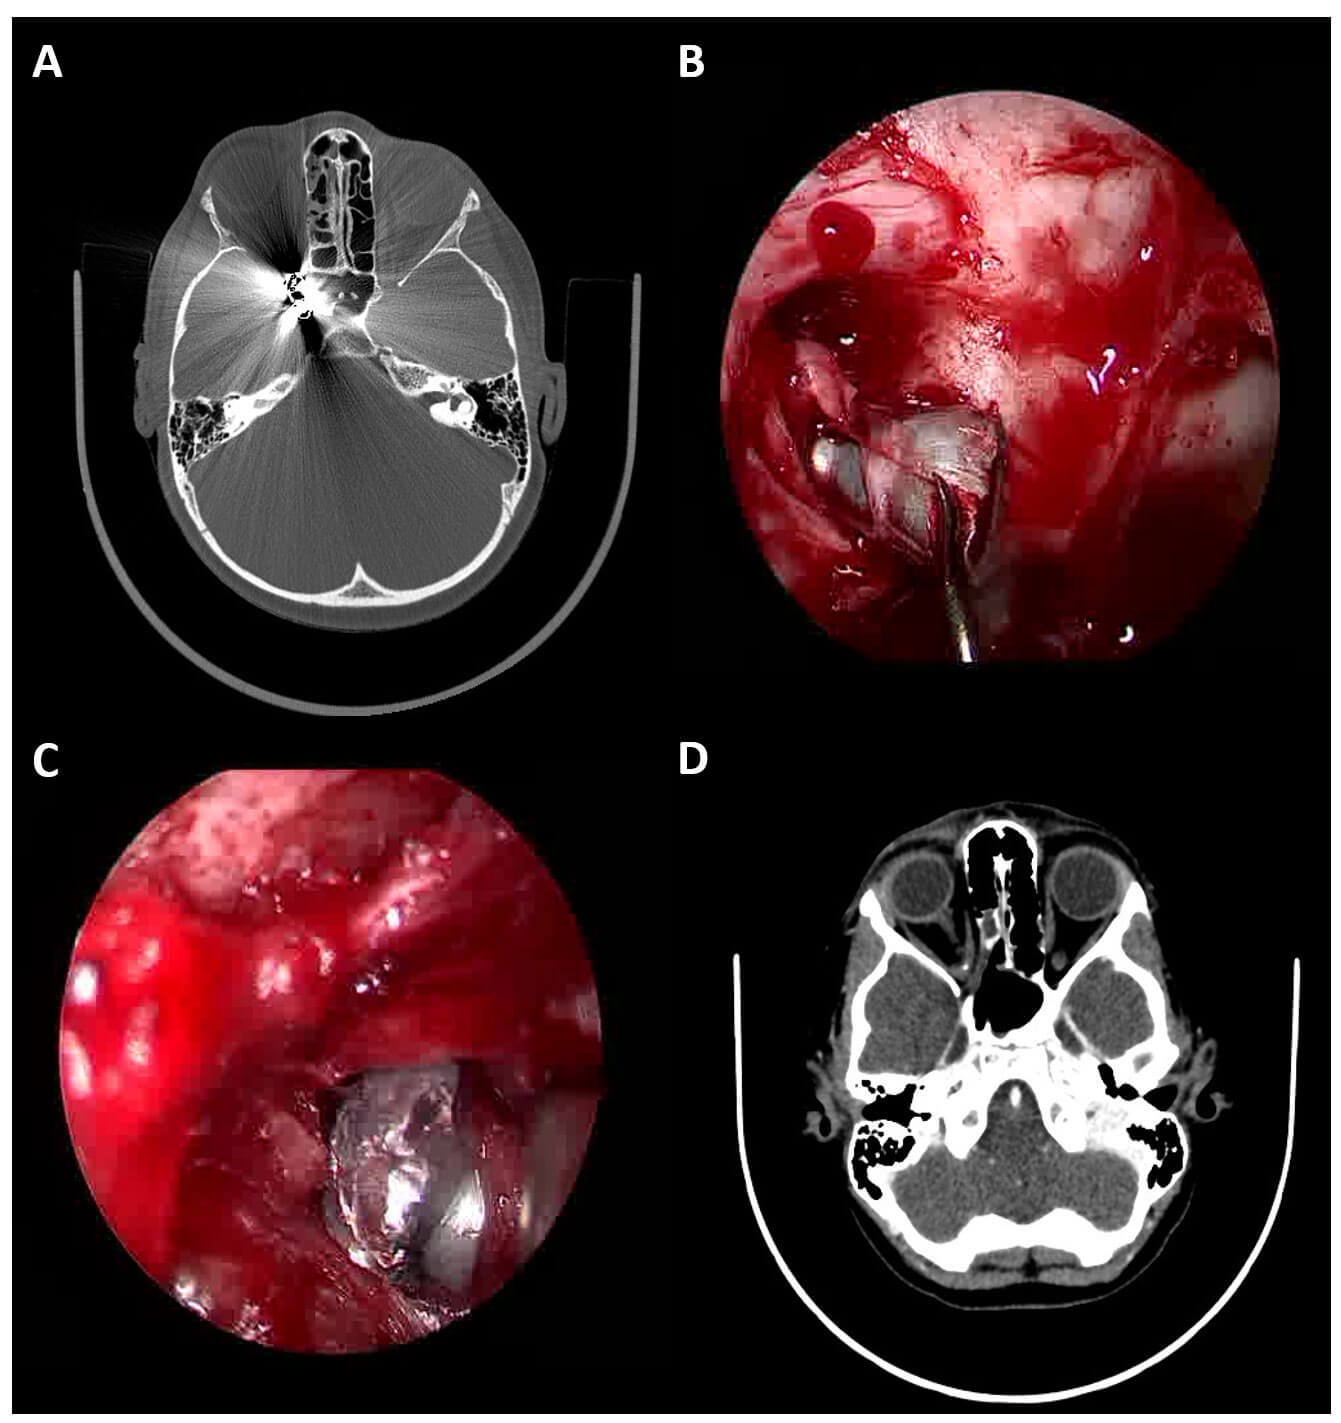

Figure 5: (a) axial plain CT head (bone window) showing two metallic foreign bodies at the orbital apex and within the optic canal; (b) endoscope image of pellet being extracted from the orbital apex via a trans-nasal route; (c) endoscope image of a second pellet being extracted from the orbital apex via a superior skin crease approach; (d) follow up axial CT head (brain window) showing retained small metallic fragments following removal of the two large pellets.

Initial investigation involved plain CT head (Figure 5a) which showed two pellets located at the orbital apex in the path of the optic nerve. There were comminuted fractures of the lamina papyracea and radiopaque fragments were seen in the medial orbit. Intracranially there was evidence of subarachnoid haemorrhage. Oral co-amoxiclav and metronidazole were started along with oral prednisolone (doses adjusted for weight). The patient was admitted for observation and over the coming days the vision became no perception of light (NPL). The complete ophthalmoplegia persisted. These findings are consistent with severe damage to the optic nerve and cranial verves III, IV and VI at the orbital apex.

The decision was taken to attempt surgical removal of the pellets despite the poor visual prognosis in order to provide pellets for evidence to the police and because the constituents of the pellets were unknown. Given the young age of the patient, it was felt that the possibility of lifelong lead exposure made surgical removal the optimal management plan. Due to the previous failed pellet extraction using a transconjunctival approach, a combined trans-skin crease and trans-nasal approach was taken as a combined case involving ophthalmology and otorhinolaryngology. Two pellets were recovered (Figures 5b, c). Follow up CT head and orbits revealed persistent small metallic fragments within the right orbit (Figure 5d). MRI will therefore be contra-indicated lifelong as these multiple tiny fragments will not be retrievable.